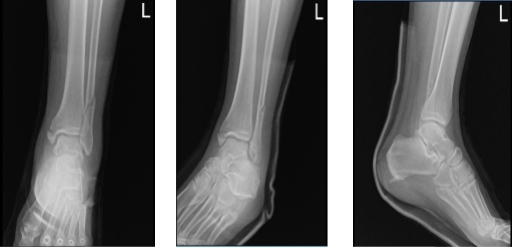

Case Study: ORIF: Lateral Malleolus Plate and Interfragmentary Screw, Medial Malleolus Screws using Fluoroscopy in a 60 year-old male

The patient is a 60-year-old male who was seen in the office following a fall from the roof. He had pain and swelling of the left ankle. He was seen by another doctor and discussed treatment options including surgical and nonsurgical. But he declined surgery at that time. He was seeing another provider as a second opinion.

We reviewed x-rays and discussed treatment options and the surgical and nonsurgical treatment options. The patient opted for surgical management. The patient has recently recovered from COVID and has a history of blood clots, for which he was on Eliquis, which he has stopped recently.

Left ankle X-ray complete 3 or more views